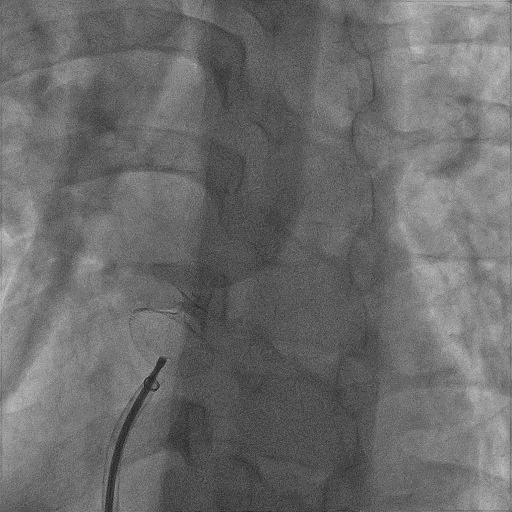

選擇D-shufo? 24/24-3封堵器,充分排氣后,沿鞘管送入左心房,在左心房釋放左房側(cè)盤面和腰部,將輸送鞘和封堵器輸送鋼纜一同后撤至房間隔,在右心房釋放右房側(cè)盤面;TTE下再次確認(rèn)位置,經(jīng)X線透視(左前斜位45°~60°)觀察封堵器形態(tài)、位置良好,無殘余分流且不影響房室瓣活動(dòng),輕輕推拉封堵器后,形態(tài)、位置無變化,逆時(shí)針旋轉(zhuǎn)輸送鋼纜,釋放封堵器。撤出輸送鞘管,手術(shù)順利結(jié)束。

輸送封堵器

釋放左盤面